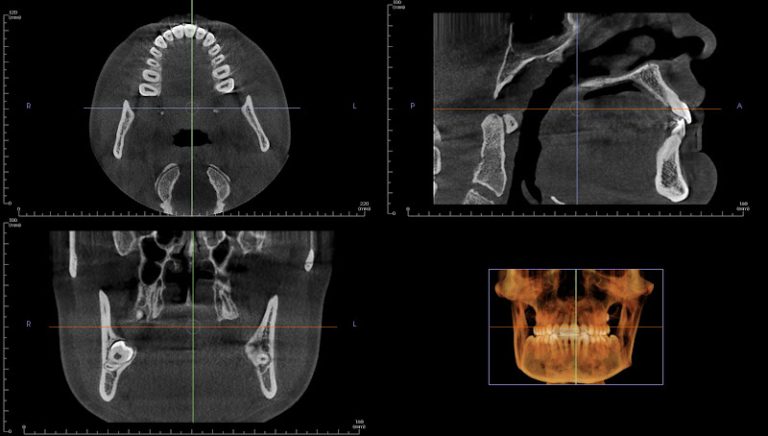

- Technology: Committed to using advanced dental technology for superior treatment outcomes.

- Advanced Technology: Utilizing the latest dental technology to ensure high-quality, efficient treatments for all procedures.